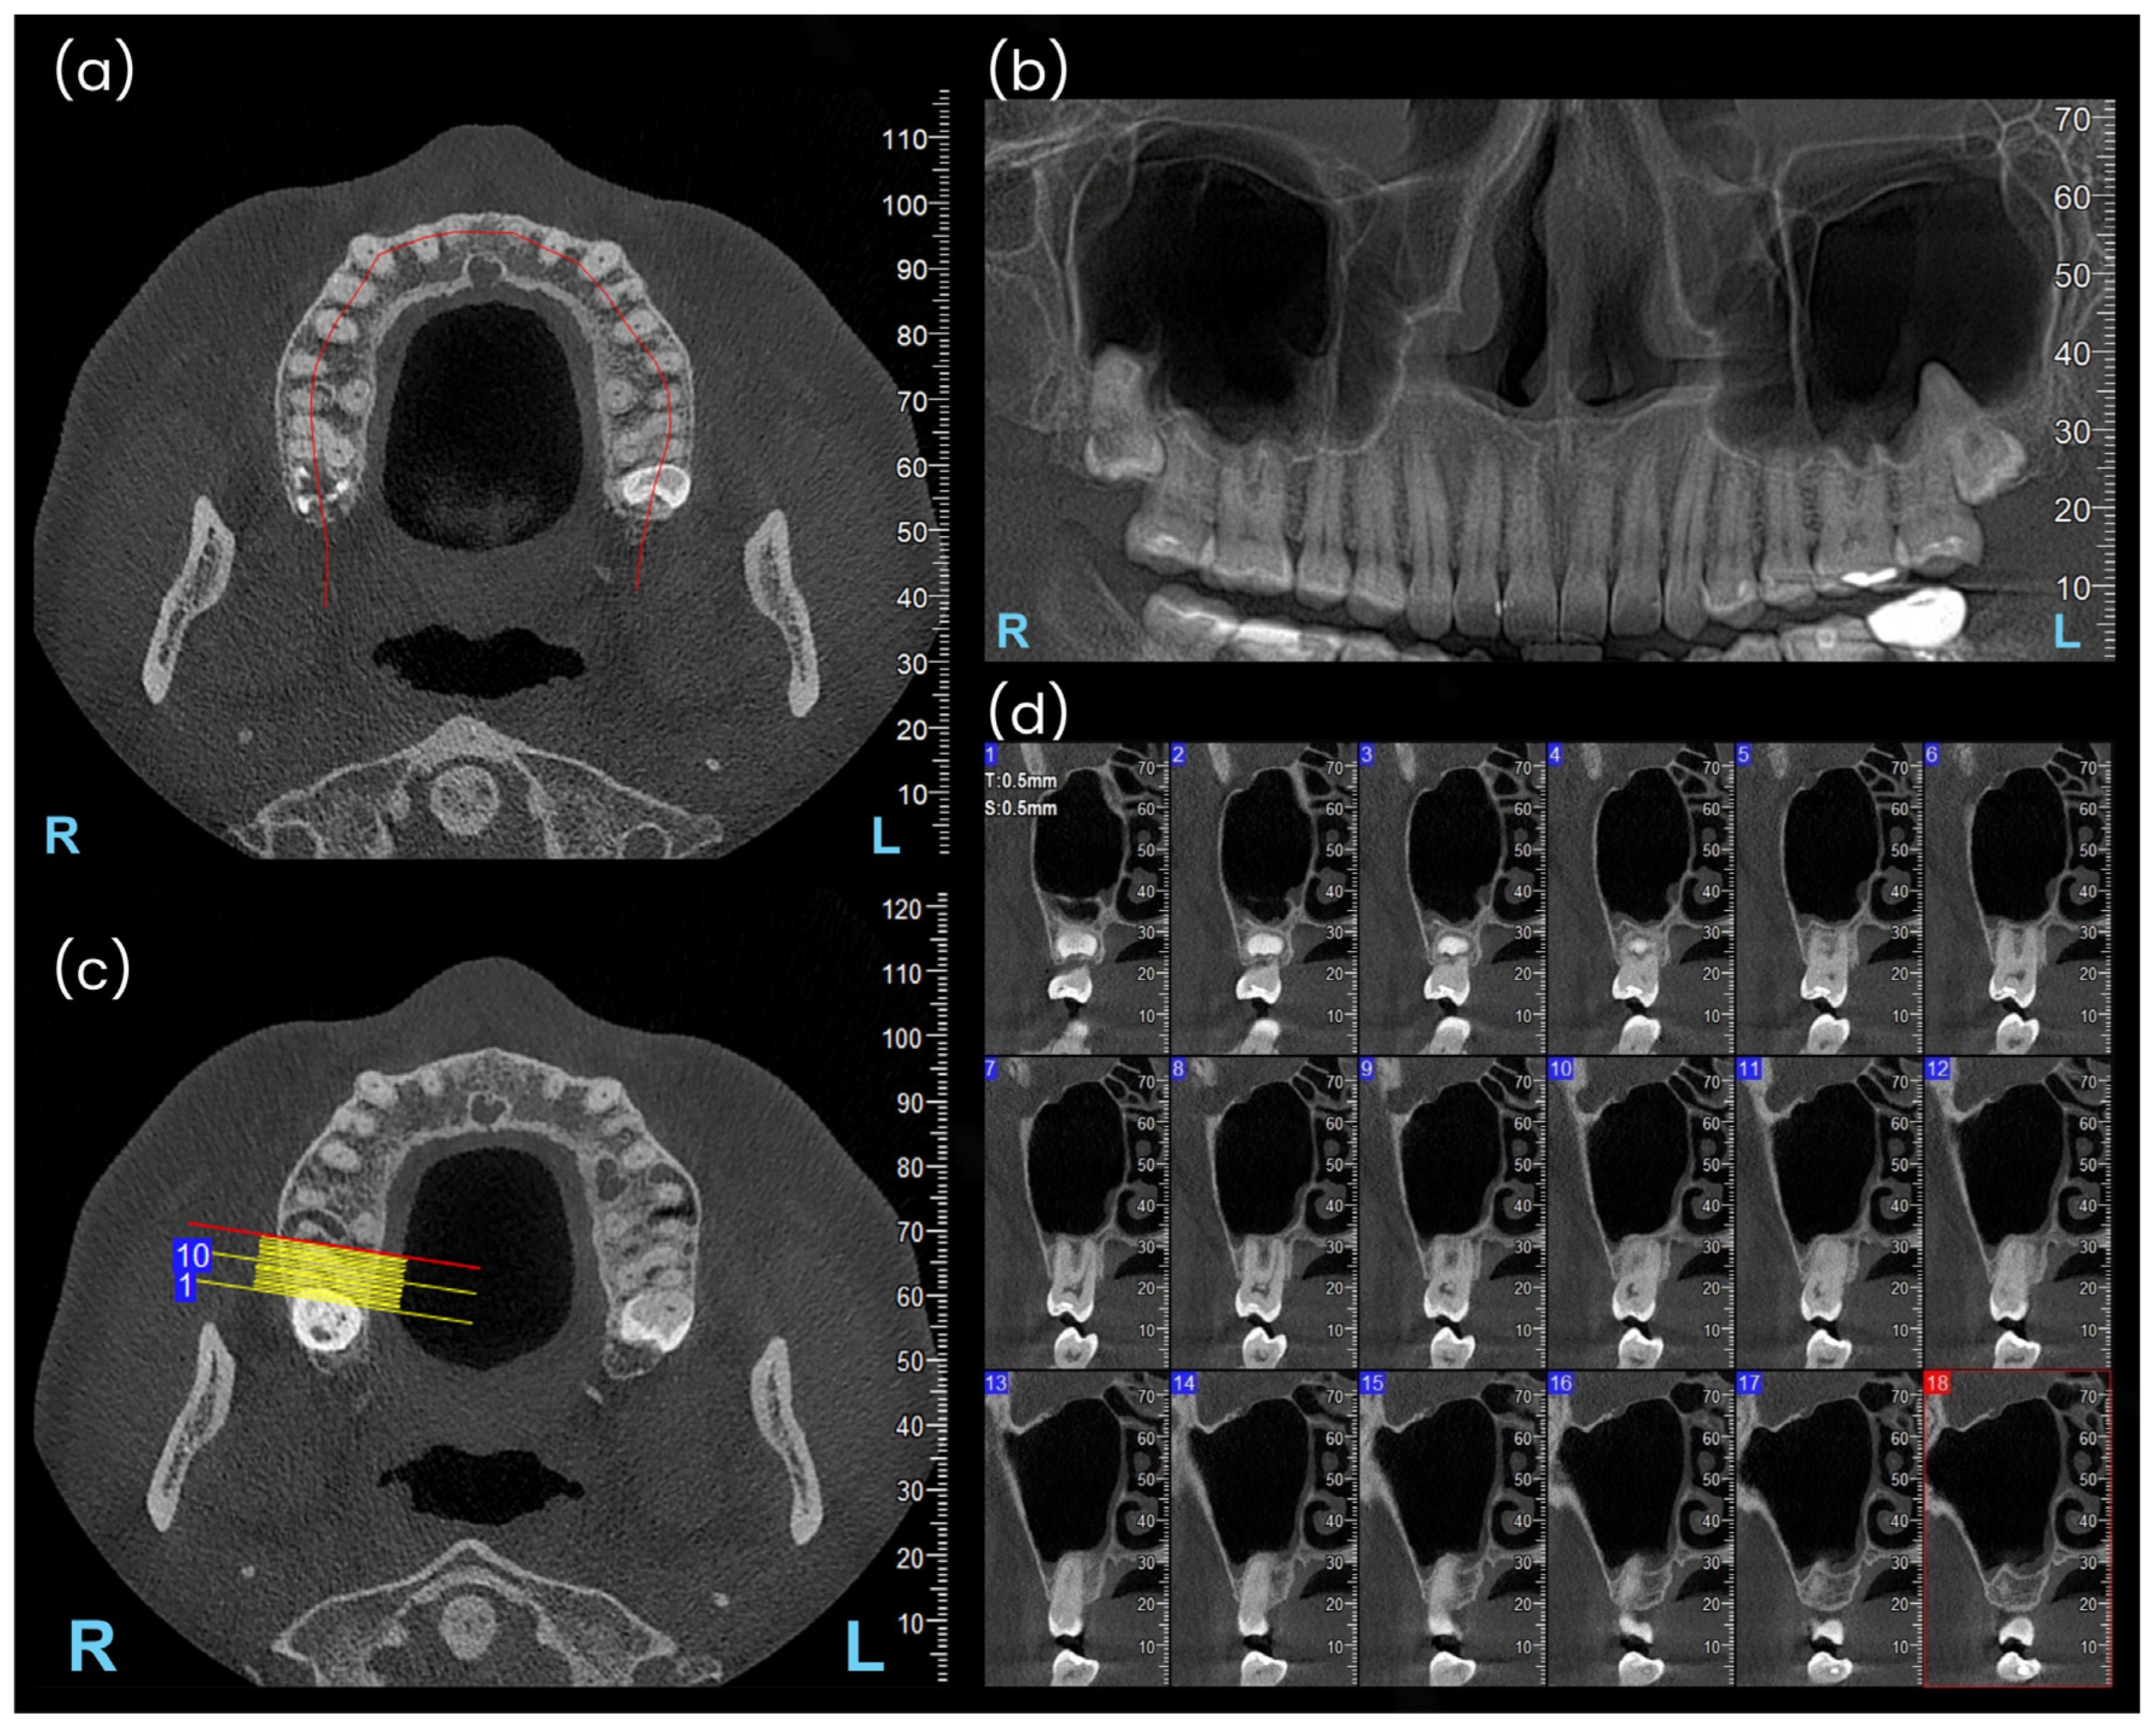

- Type I: Penetrating relationship—the tooth root extends into the maxillary sinus cavity (Figure 2).

- Type II: Tangential relationship—the tooth root is located 0–0.20 mm from the sinus floor (Figure 3).

- Type III: Close relationship—the tooth root is located 0.21–2 mm from the sinus floor (Figure 4).

- Type IV: Spaced relationship—the tooth root is located more than 2 mm from the sinus floor (Figure 5).